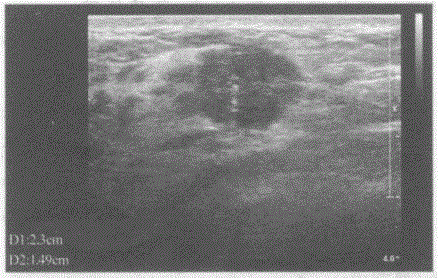

问题 临床资料:女,28岁,查体时发现右乳腺一肿物,活动度差,质硬。 超声综合描述:右乳外上象限可见2.0cm×1.5cm低回声区,形态欠规则,边界不平呈锯齿状,内回声不均,可见点状强回声,CDFI:内可见较丰富点棒状动静脉血流信号,V31.0cm/s。见下图及彩图。 {图2} 超声提示:

选项 A.乳腺炎 B.乳腺癌 C.乳腺脓肿 D.乳腺纤维腺瘤

答案 B